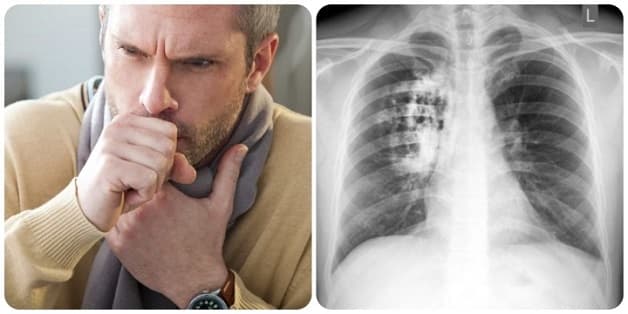

Ung thư phổi thường không có dấu hiệu nhận biết rõ ràng ở giai đoạn đầu. Nếu xuất hiện triệu chứng nghĩa là bệnh đã ở giai đoạn muộn và bạn cần đến cơ sở y tế để thực hiện thăm khám ngay lập tức. Dấu hiệu khi mắc ung thư phổi bao gồm:

– Sốt, ho khám và khó thở, có thể ho ra máu.

– Cơ thể mệt mỏi, sụt cân không rõ nguyên do, ngón tay bị hiện tượng dùi trống.

– Khi mắc ung thư phổi có thể xuất hiện các triệu chứng như đau ngực, đau xương, khó nuốt, đau đầu và buồn nôn do các tế bào ung thư ảnh hưởng đến những cơ quan khác.

Chẩn đoán hình ảnh trong ung thư phổi sẽ giúp cho bác sĩ quan sát được tình trạng bên trong phổi như những tổn thương, các khối u nếu có, mà không cần dùng đến biện pháp xâm lấn. Có 2 phương pháp chẩn đoán hình ảnh phổ biến giúp thực hiện tầm soát ung thư phổi là chụp X-quang và chụp cắt lớp CT. Cả 2 phương pháp trên đều sử dụng tia X để thực hiện do đó phụ nữ mang thai không nên thực hiện vì có thể ảnh hưởng đến em bé trong bụng.

Chụp X-quang phổi giúp phát hiện những tổn thương và các khối u xuất hiện bên trong phổi